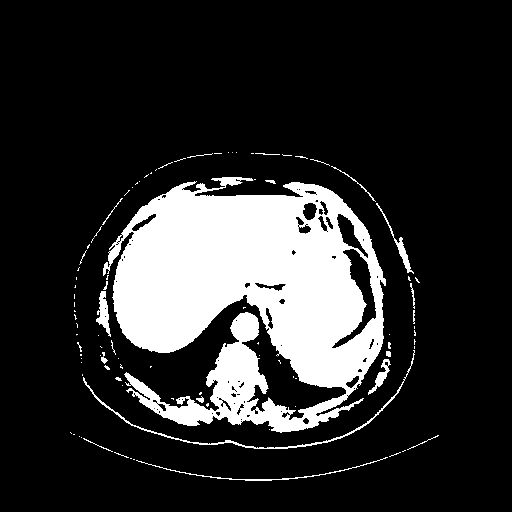

Generated VENOUS CT scan (A→B translation)

Full window (WL 1023.5, WW 4095 β†’ Low βˆ’1024, High +3071)

Actual HU range: [-1024.0, 3071.0]